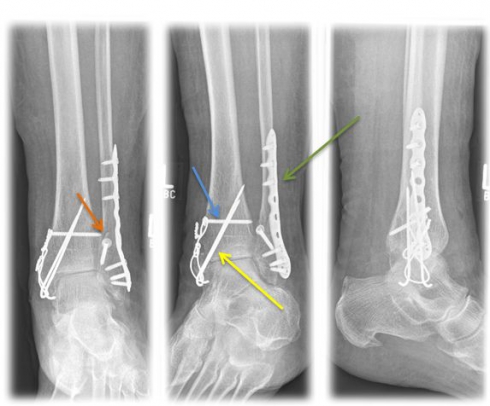

Method of choice in surgical therapy

• Internal ankle fracture: mostly use of cannulated screws or tension belt osteosynthesis

• Outer ankle fracture: usually insertion of a lag screw and a neutralization plate

• tape seam may be necessary if the inner tape can be folded out

• In case of syndesmosis injury, the insertion of an adjusting screw is necessary for 6 weeks to stabilize the syndesmosis.

undefined

Fig. 4) Osteosynthetic treatment of a bimallel ankle fracture by means of tension belt osteosynthesis at the inner ankle (yellow arrow), neutralization plate (green arrow) and a traction screw (orange arrow) at the outer ankle as well as an adjusting screw (blue arrow).